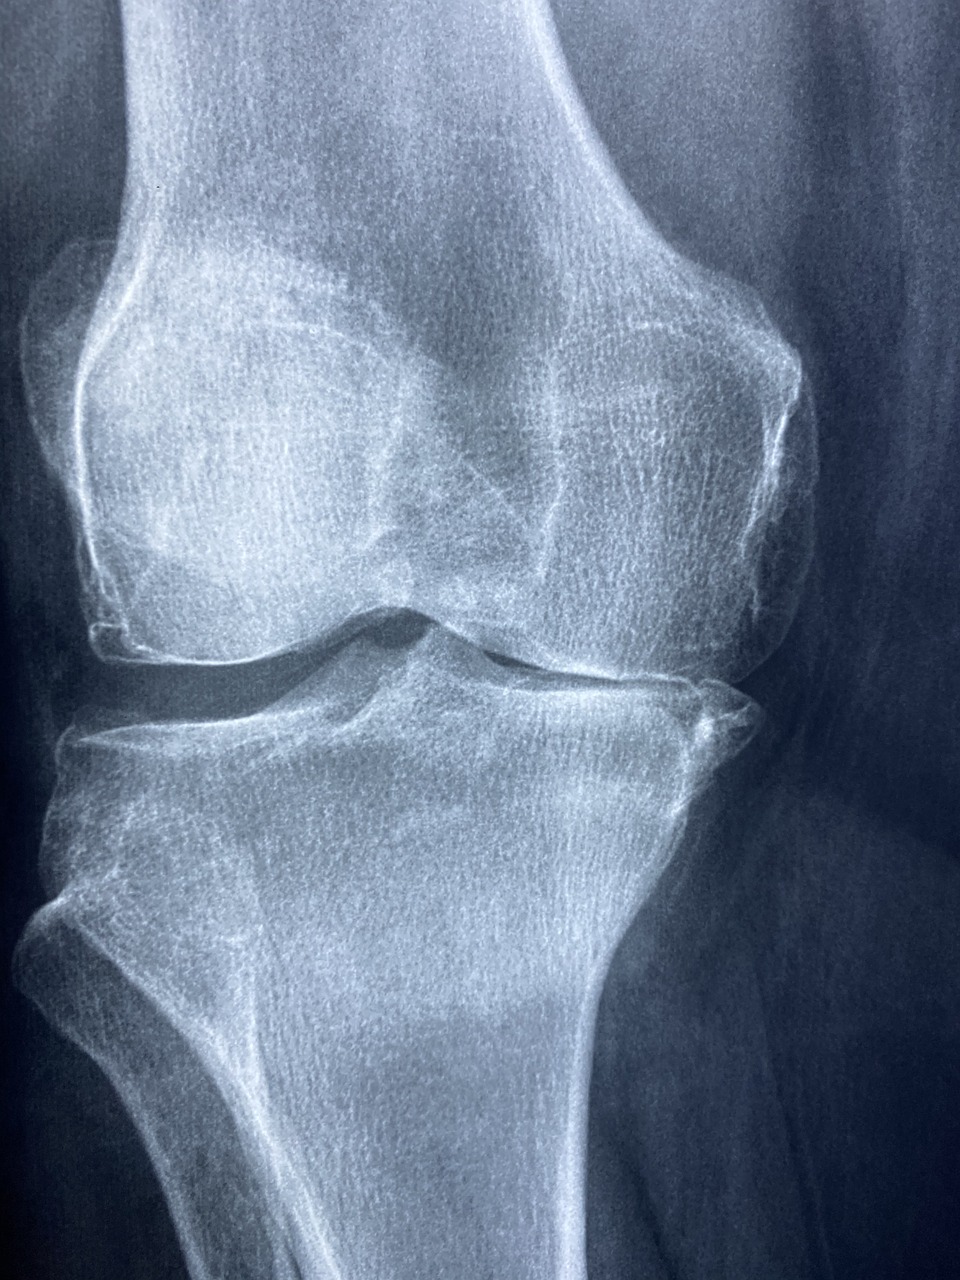

증상이 발현되어 병원에 가면 먼저 X-ray 촬영을 하고 필요한 경우 초음파 검사나 피검사를 하여 진단하게 되는데요, 연골은 신경이 없어서 통증을 느낄 수 없다고 합니다. 통증은 뼈와 뼈를 감싸고 있는 활막에 신경이 많아서 생깁니다.